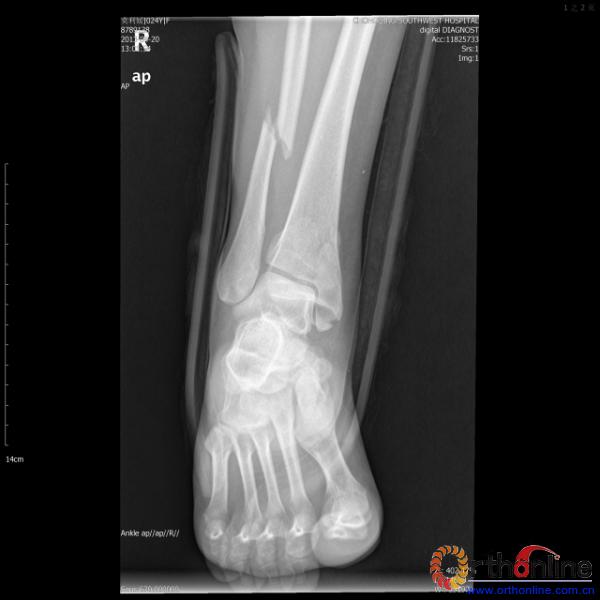

伤员和家属迅速赶到西南医院,10点关节外科段小军副教授查看伤员后急诊收入院,拍摄X片和急诊行三维CT重建检查,提示踝关节创伤严重,出现三踝骨折伴胫距关节脱位,需要急诊手术治疗。随后段教授与正在四川成都参加“汶川地震5周年灾害医学救治研讨会”的杨柳主任联系,进一步完善救治方案。地震当晚,段教授为该伤员进行急诊手术,手术顺利对复杂骨折进行了解剖复位,有效的钢板螺钉固定。术后伤员的疼痛明显缓解,复查X片,踝关节结构恢复满意。

患者术前X片(一)